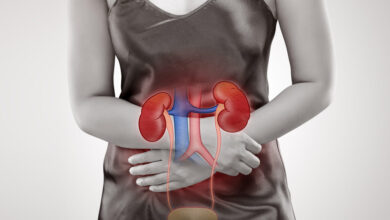

الكلى وأمراضها

الكلى وأمراضها توصيات يومية تخفف من خطر الإصابة رغم صغر حجمها الا ان للكلى دور اساسي في جسم الإنسان، فهي…

السكري… سبب 40% من حالات الفشل الكلوي

السكري… سبب 40% من حالات الفشل الكلوي شهدت علاجات داء السكري تطورات ملحوظة في السنوات الاخيرة بفضل الأبحاث والدراسات المستمرة…